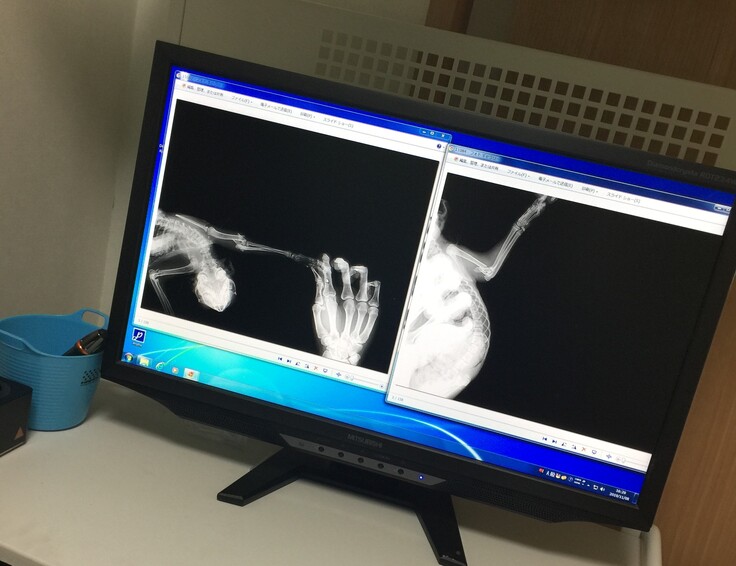

【活動報告】卒業猫ちゃん、手を骨折していためめちゃんの物語

左前足が骨折していました

約1ヵ月ギブスで生活することに